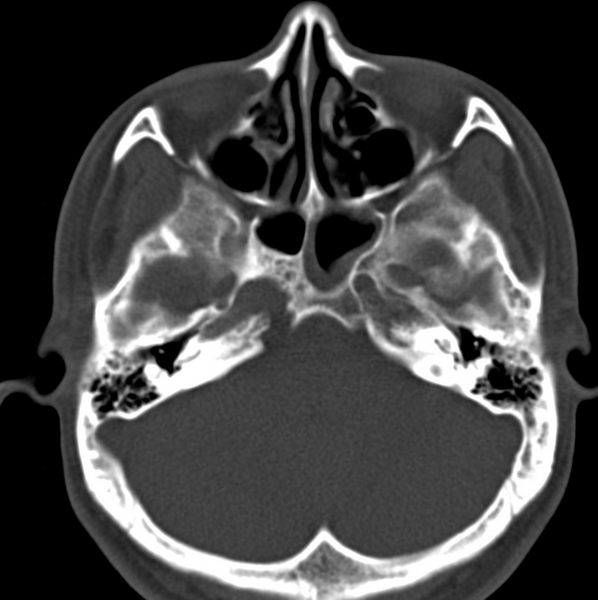

男、31、鼻咽部肿瘤放疗后请帮忙看看。

效果好,右侧破裂孔扩大,局部骨质缺损,为颅底骨质破坏。

1)鼻咽部肿瘤侵犯颅底放疗术后改变。2)左侧蝶窦炎。

咽后壁增厚,左侧咽鼓管隆突增大、咽鼓管咽口变浅,同侧咽旁间隙较窄。右侧颅底骨质破坏?为什么不在同一侧?

鼻咽部肿瘤侵犯颅底放疗术后改变.